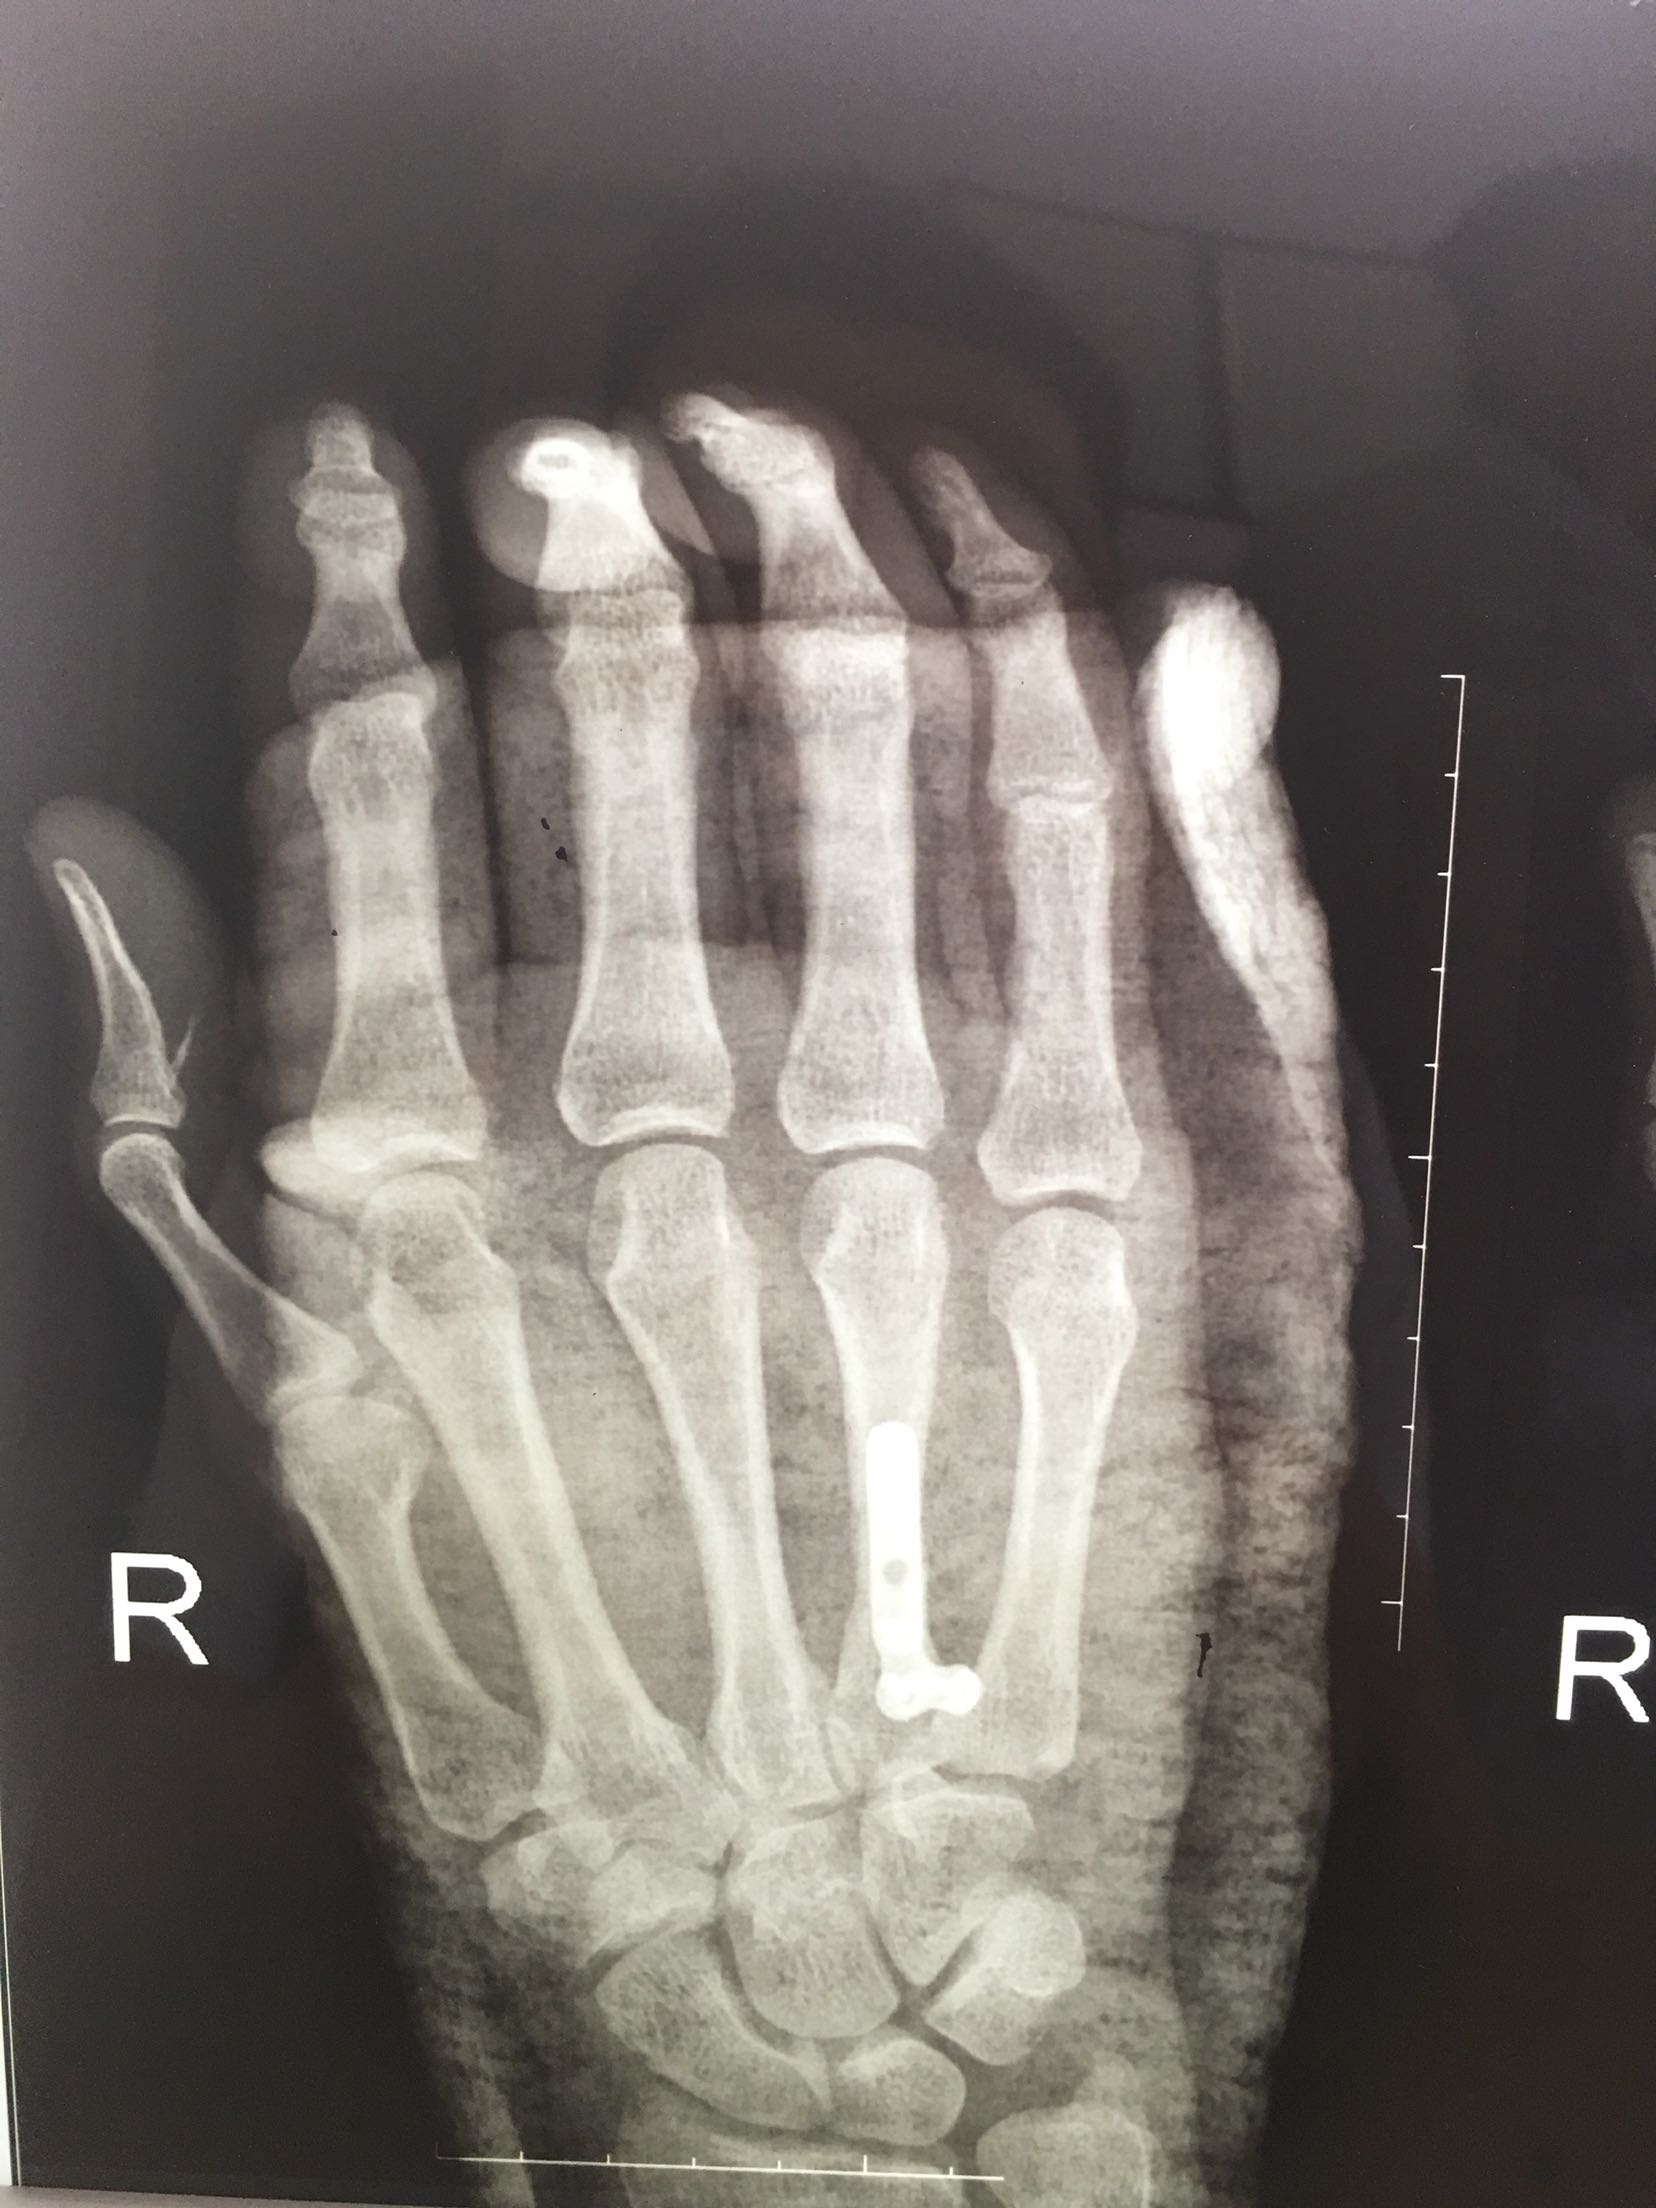

掌骨骨折微钢板固定

患者,男,52岁,摔伤后右手肿痛,活动受限4小时入院。

右手掌肿胀明显,皮色皮温正常,局部压痛,纵叩痛阳性,可及骨擦感,第四掌指关节活动受限,末梢血运感觉正常。

诊断 处理

完善检查,在臂丛麻醉下行切复内固定术,术后抗炎,消肿止痛处理。

钢板固定的手术风险?望各位老师指正?谢谢